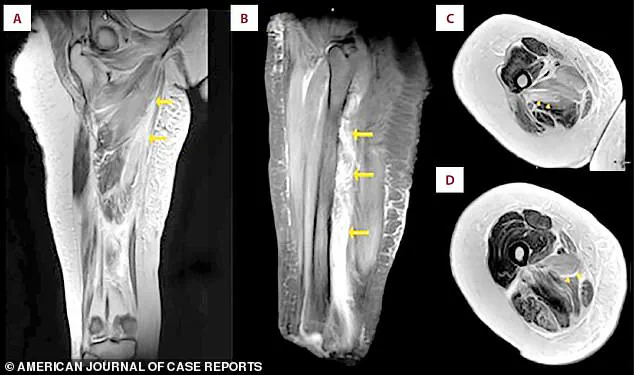

An MRI scan of the patient's right thigh revealed widespread muscle swelling.

The images, marked with arrows, pinpointed this fluid buildup in the inner thigh muscles (the adductor group) and, in a different view, showed similar swelling affecting the muscles at the back of the thigh.

These scans provided a visual confirmation of the internal devastation caused by rhabdomyolysis, highlighting the extent of the damage that had occurred in the absence of visible external injury.